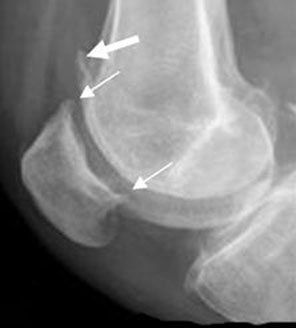

Os osteófitos são visíveis na radiografia em forma de uma protuberância óssea (um “chifrinho”). Habitualmente, os osteófitos em si não necessitam nenhum tratamento.

O que é importante é diagnosticar e tratar a artrose e suas consequências musculares, tendíneas e ligamentares em torno da articulação, para que a pessoa volte a ter um estilo de vida saudável. Abaixo, algumas imagens de livros e em raios-x, pra que agora todos possam identificar um osteófito quando for mencionado pelo profissional da área de saúde que lhe está atendendo.

No calcanhar, o osteófito é conhecido por esporão. E pode dar embaixo do pé ou na direção do tendão de Aquiles. Ocorre por tração excessiva de algum dos tendões ou fáscia.

Os dois possíveis tipos de osteófitos no calcanhar, vistos pelos raios-x. O de cima, por excesso de tração do tendão de Aquiles. O de baixo, por excesso de tração da fáscia plantar.